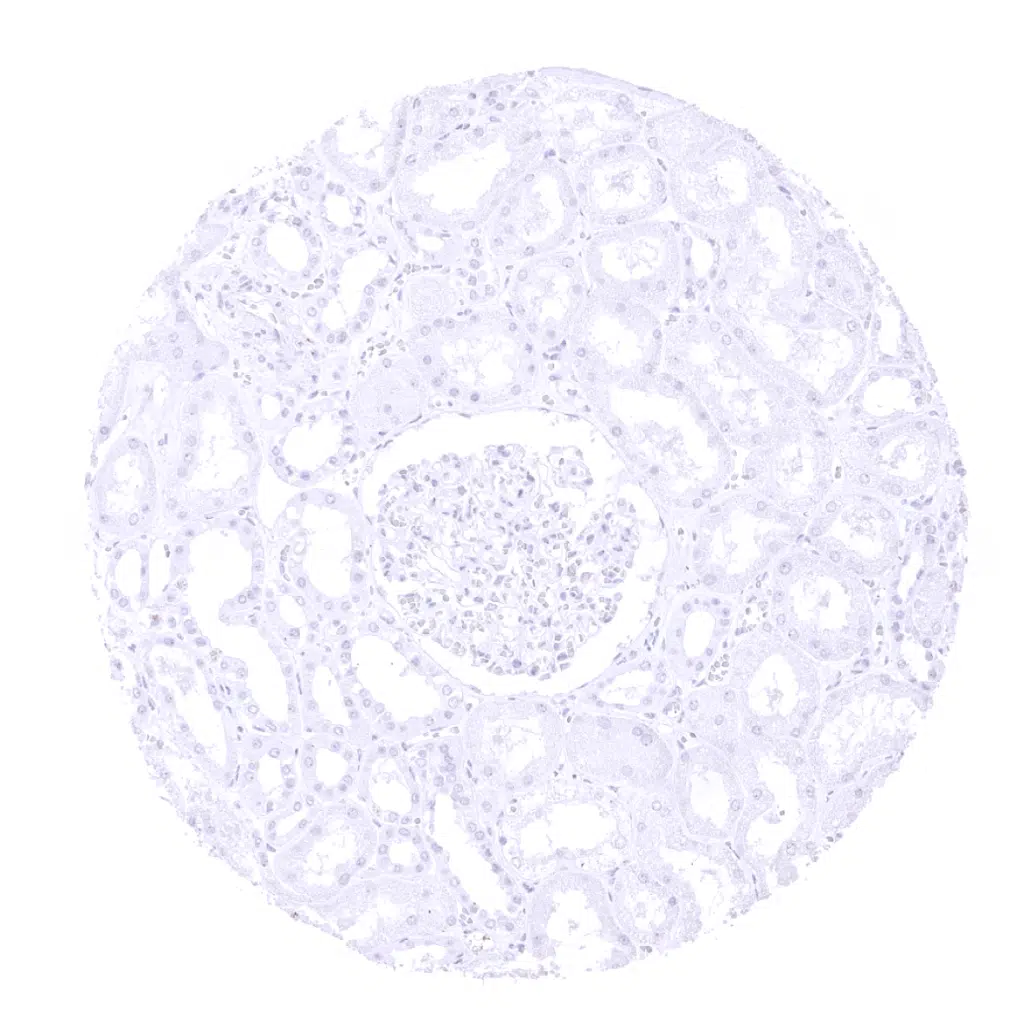

Desmin antibody [MSVA-651M] HistoMAX

Kidney, cortex